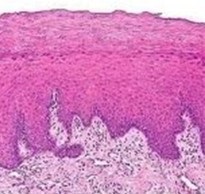

manifestare microscopica a CPL

Leziunile tipice includ giperortokeratoz giperparakeratoz sau strat granular îngroșare, acantoza, cu strat intercelular edem spinos, necroza sau degenerare lichid a celulelor din stratul bazal, cu apariția unei benzi eozinofilice descompunere subțire omogenă în locul stratului bazal și infiltrarea limfocitelor și a celulelor plasmatice strat de țesut conjunctiv subepitelial separat. Manifestarile diskeratoza nu sunt marcate.